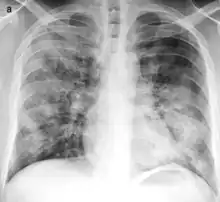

Bronchopneumonia

Bronchopneumonia is a subtype of pneumonia. It is the acute inflammation of the bronchi, accompanied by inflamed patches in the nearby lobules of the lungs.[1]

It is often contrasted with lobar pneumonia; but, in clinical practice, the types are difficult to apply, as the patterns usually overlap.[2] Bronchopneumonia (lobular) often leads to lobar pneumonia as the infection progresses. The same organism may cause one type of pneumonia in one patient, and another in a different patient.